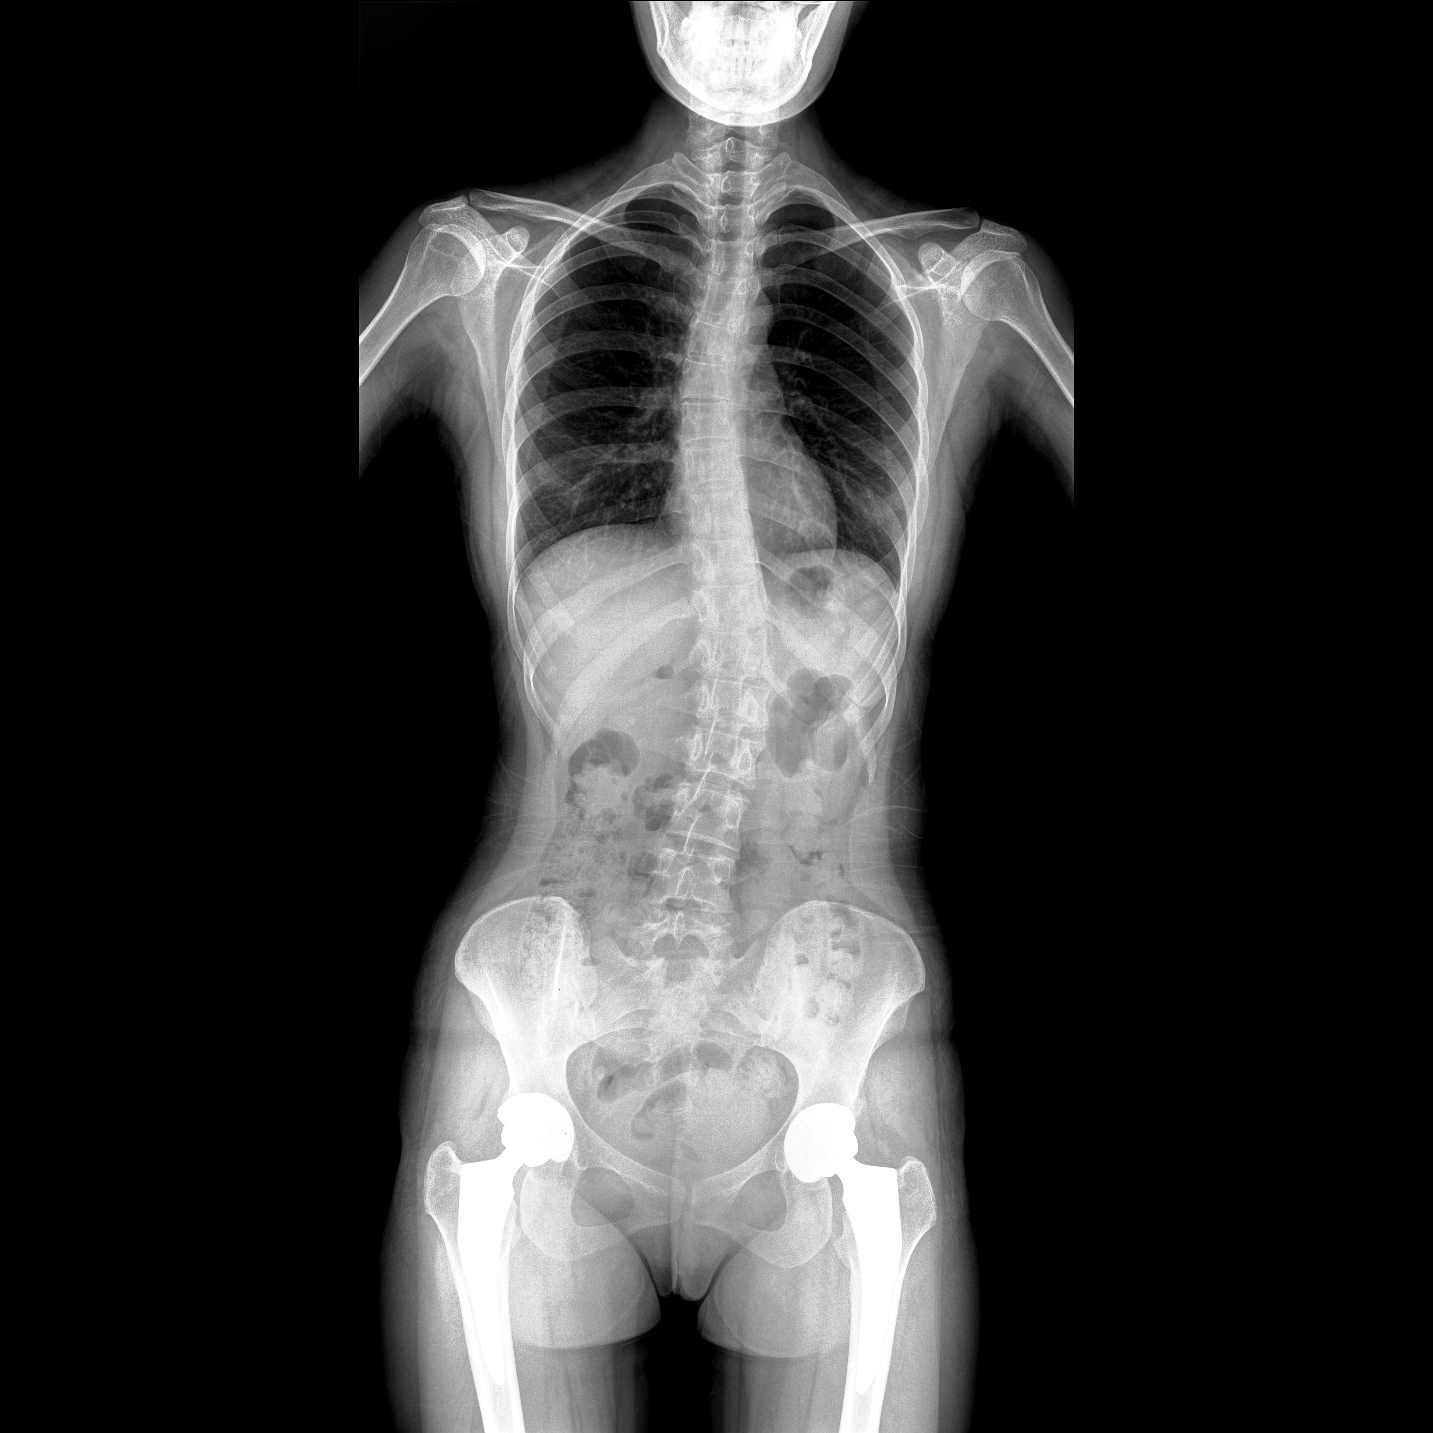

支持全脊柱攝影、雙下肢攝影、脊髓造影、復(fù)雜創(chuàng)傷、人工關(guān)節(jié)置換、關(guān)節(jié)損傷的修復(fù)重建等大視野臨床應(yīng)用

17"*34"有效視野,一次成像不拼接。相較于多張攝影再軟件拼接的DR設(shè)備,PLX8600解決了拼接圖像存在密度不均勻,拼接處圖像配準(zhǔn)和放大效應(yīng)等問(wèn)題,給臨床帶來(lái)了大視野影像解決方案,可一次性覆蓋全脊柱或雙下肢影像。